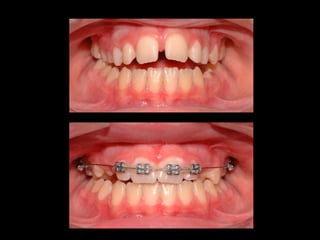

BARRA PALATINA CORRIGIENDO LA ROTACIÓN MOLAR SE PUEDE GANAR 1-2 MM DE LONGITUD DE ARCADA POR LADO

BARRA PALATINA CORRIGIENDOLA ROTACIÓN MOLAR SE PUEDE GANAR 1-2 MM DE LONGITUD DE ARCADA POR LADO